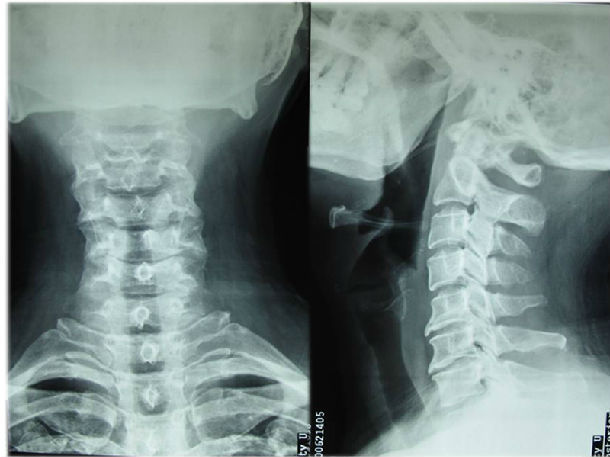

颈椎ct片子图解

颈椎ct片子图解,颈椎ct图片片子

伤后颈椎ct

7mm,左侧约1.8mm.颈椎正侧

颈椎x光片